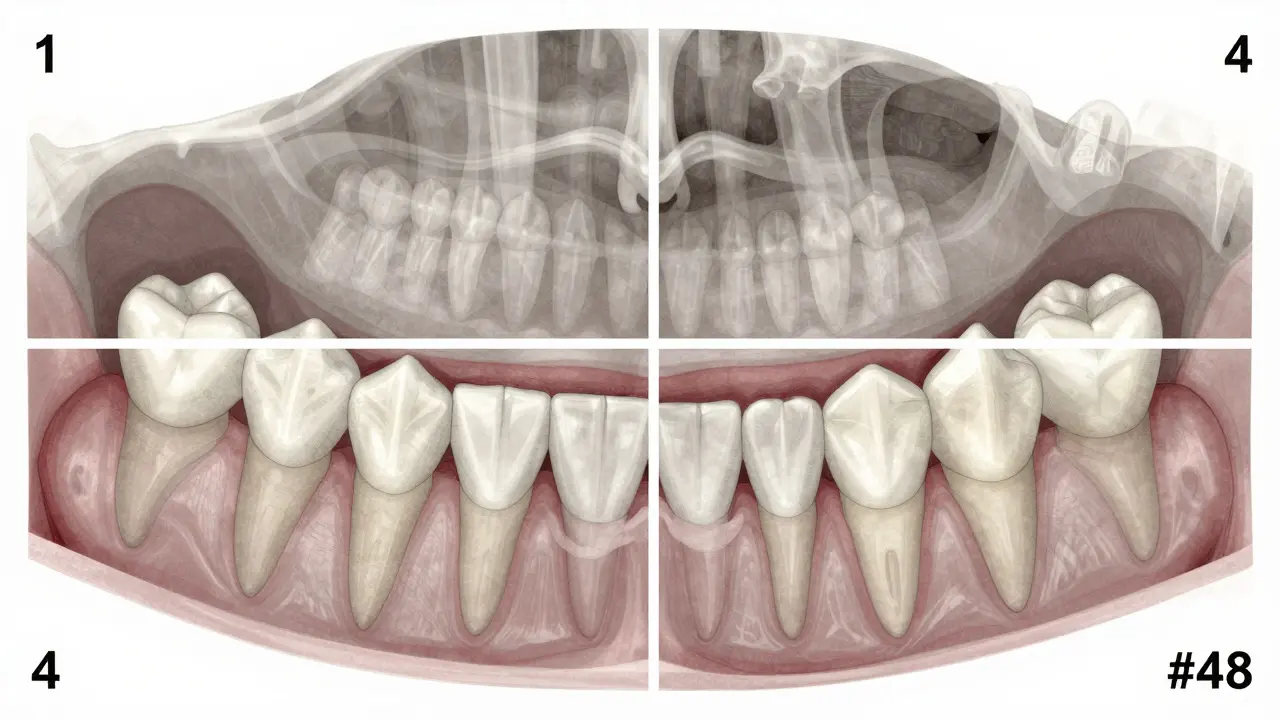

Zubní čísla nejsou náhodná. Každý zub v ústní dutině má svůj jedinečný kód podle mezinárodního systému FDI (Fédération Dentaire Internationale). Tento systém rozděluje ústní dutinu na čtyři kvadranty: horní pravý, horní levý, dolní levý a dolní pravý. Každý kvadrant má číslo od 1 do 4. Poté se každý zub v kvadrantu čísluje od 1 do 8, začínaje u středního řezáku a konče posledním molárem.

Takže:

• 1 = horní pravý kvadrant

• 2 = horní levý kvadrant

• 3 = dolní levý kvadrant

• 4 = dolní pravý kvadrant

A pokud vezmete číslo kvadrantu a přidáte číslo zubu, dostanete unikátní identifikátor. Zubaři používají tento systém, protože je přesný a nezávisí na tom, zda je pacient levák nebo pravák. Zubař v Praze a zubař v Ostravě budou mluvit o stejném zubu, i když ho nazývají jinak.

Zub 48 tedy znamená: kvadrant 4 (dolní pravý) a zub číslo 8 (poslední molár). To je ono - třetí molár, který lidé obvykle nazývají moudrostním zubem.

Na rentgenovém snímku to vypadá jako kdyby zub byl „zakopaný“ pod dásní nebo kostí. To není nemoc. Je to jen přirozená variace lidského těla. Ale pokud způsobuje bolest, zánět nebo tlačí na jiné zuby, je potřeba zvážit jeho odstranění.

Anatomický náčrt čelisti s označenými kvadranty a pozicí zubu 48 v dolním pravém kvadrantu.

Naopak, pokud máte zub 48, ale nevyrůstá, může to být problém. Pokud je zakopaný pod kostí a tlačí na kořen sousedního zubu (zub 47), může způsobit jeho poškození. To se dá vidět na rentgenu. Zubař to říká jako „impaktovaný zub“. Pokud to vypadá, že zub 48 bude tlačit na zub 47, je lepší ho odstranit, než čekat, až zub 47 začne bolet.

Všechny dospělé, kteří mají kolem 16-20 let, by měli mít ortopantomogram (panoramický rentgen). To je jednoduchý snímek, který ukazuje všechny zuby, včetně těch, které ještě nevyrůstaly.